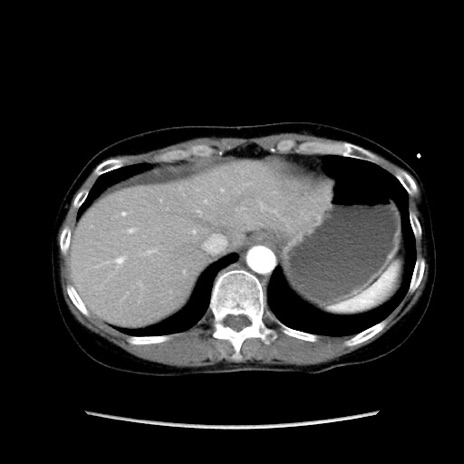

症例32(横断像)

【症例】40歳代 女性

【主訴】上腹部痛、嘔気・嘔吐

【現病歴】約9時間前頃から急に上腹部痛、嘔気、嘔吐が出現。改善しないため救急要請。

【既往歴】子宮頚癌(広汎子宮全摘術、放射線療法)、腸閉塞

【身体所見】腹部:平坦、軟、腸雑音亢進、上腹部を中心に腹部全体に圧痛あり。

【データ】WBC 8400、CRP 0.03